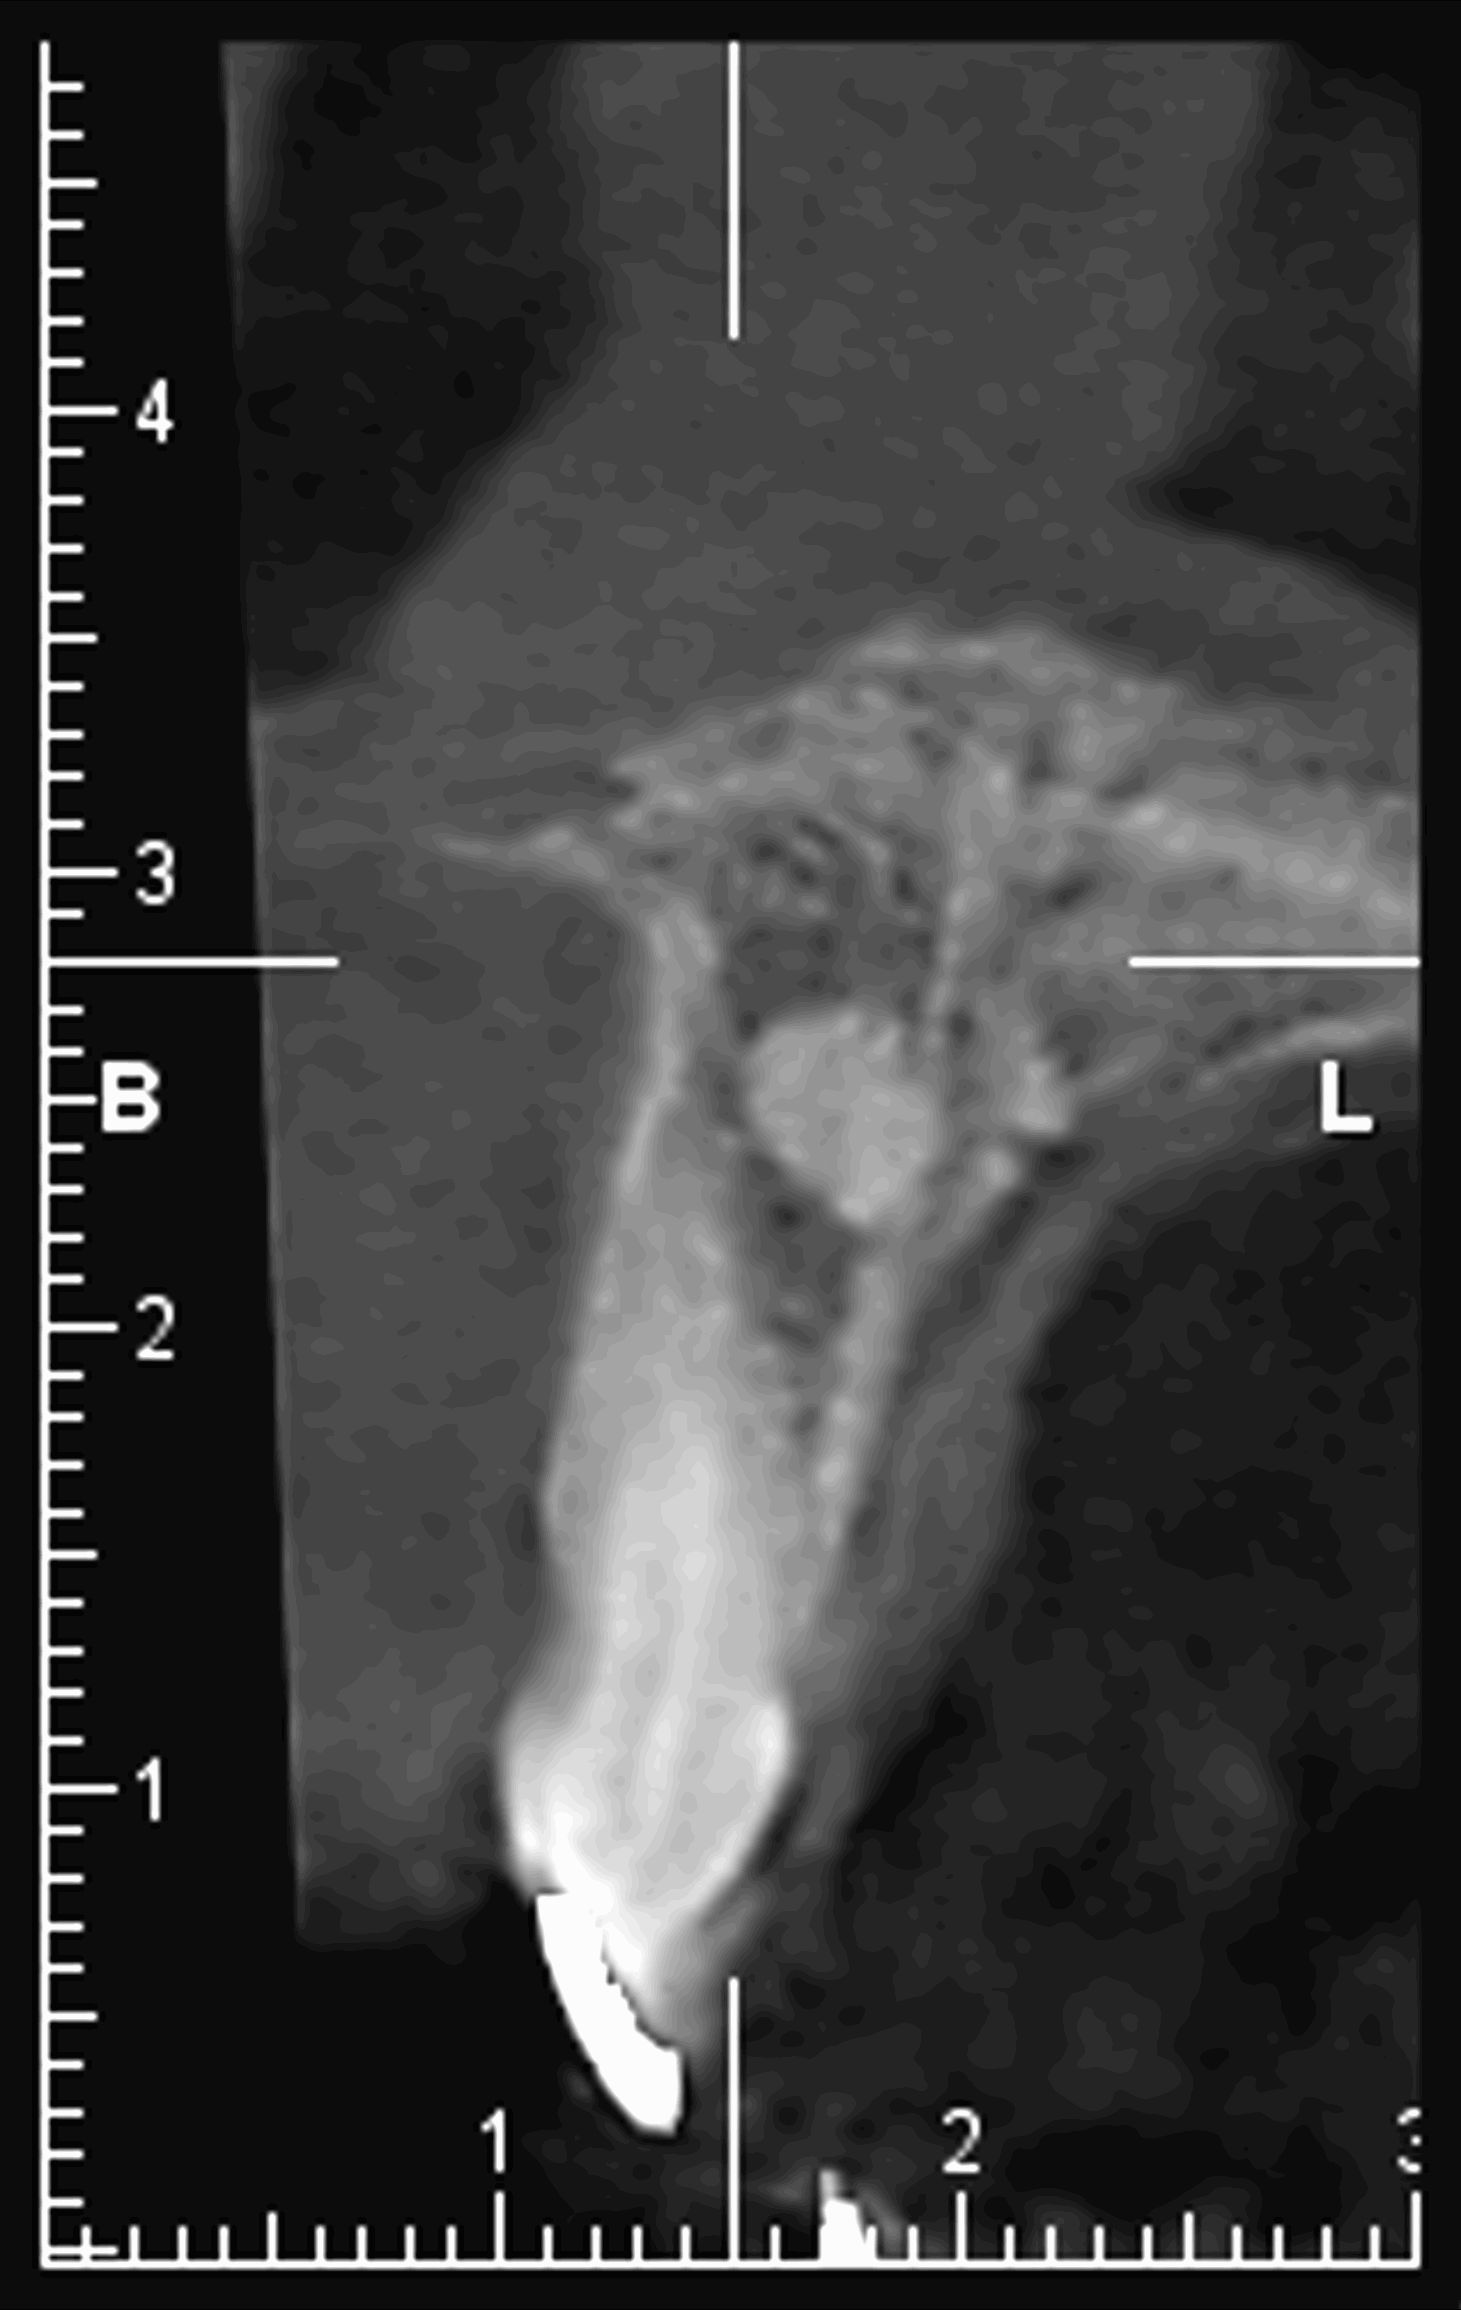

Le cone beam est une nouvelle technique de radiographie numérisée situé entre le panoramique dentaire et le scanner, il utilise un faisceau d’irradiation de forme conique d'où son nom. Cet appareil présente notamment l’avantage d’être plus précis que le panoramique dentaire et il possède une résolution similaire, voire supérieure à celle du scanner, avec en plus la possibilité d’une reconstruction numérique en 3D.

Le cone beam utilisé en pathologie dentaire et maxillo-faciale est indiqué pour l’examen des tissus minéralisés (dents, cartilages, os), il permet d’identifier les lésions osseuses, les fractures, les infections, les kystes ou les corps étrangers.

Il est un examen de choix en implantologie.

Il évalue au plus juste le volume osseux et la position des structures anatomiques comme les nerfs en vue de la pose d’implants. La modélisation en 3D permet la taille et la forme des implants proportionnellement à la morphologie du patient et de simuler virtuellement leurs emplacements.

Les nouvelles générations de scanner permettent de faire une acquisition d’un volume global d’une partie du corps et de travailler à l’intérieur de ce volume en isolant une structure anatomique donnée et de l’explorer dans tous les plans de l’espace.

Grace à la technique de seuillage il est possible de dissocier progressivement les dents des structures osseuses environnantes dans le volume donné.